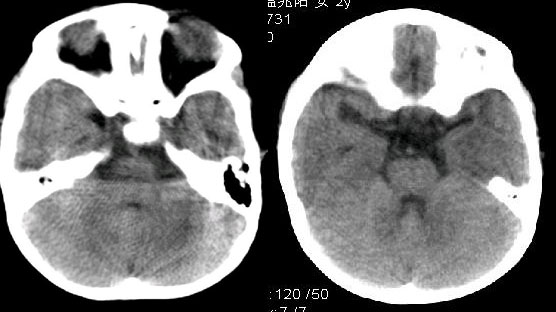

女,2岁。生后以来智力低下,长期易感冒,发烧,身体差。孕史,用药史不详!

三脑室、侧脑室扩大,脑沟裂增宽明显,尤以大脑半球为甚。胼胝体压部及膝部狭小便薄。考虑1脑小畸形

2脑萎缩[发育不全所致可能或hie]

双侧大脑大部分半球虫蚀样密度减低,脑实质呈负占位效应,脑室扩大,低密度边缘散在钙化影阴,长期易感冒,发烧,身体差,请详细询问有无发热时的抽搐病史。我觉得像是:脑炎后遗症。

本例特点:1 脑室扩大.以三脑室,四脑室扩大为主.2 脑沟 脑裂增宽,以纵裂增宽为主.3 脑实质内大量低密度影,(提示缺血及脱髓鞘变性).4 双侧顶枕部点状钙化.

结合临床考虑:1 神经皮肤综合征_结节性硬化.2 胼胝体发育不良.